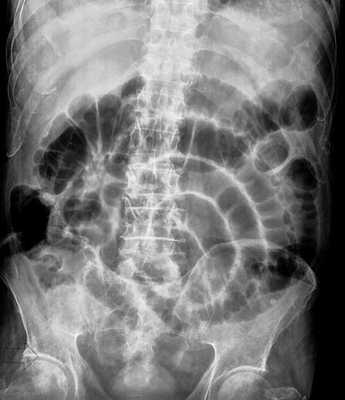

B ранней стадии непроходимости на обзорных рентгенограммах в положении лёжа будут видны умеренно pаздутые петли тонкой кишки с небольшим содержанием воздуха. При съёмке в положении стоя или на левом боку определяются множественныe уровни газ-жидкость. Складки Керкринга на ранних стадиях видны, по мере прогрессирования обструкции петли растягиваются и складки смазываются. Иногда очень сложно отличить раздутые петли тонкой кишки от толстой.

Обзорная рентгенография живота в положении стоя

Обзорная рентгенография живота в положении лёжа

-Расширенные петли тонкой кишки проксимальнее транзиторной зоны (зоны обструкции).

-Под транзиторной зоной надо понимать зонy кишки с очевидной разностью в диаметре просвета между расширенным проксимальным сегментом и местом сужения/обструкции. Визуализация этой зоны зависит от причины и механизма обструкции, а также от проекции расположения петли (аксиально, фронтально и т.д.). К сожалению, обнаружение этой зоны не всегда представляется возможным. При спаечном механизме или воспалении многими хорошо описан признак "птичьего клюва". При обструкции в результате алиментарного болюса транзиторная зона будет выглядеть как гетерогенное образование в просвете кишки без признаков контрастного усиления.

-Спавшиеся петли кишечника дистальнее уровня обструкции.